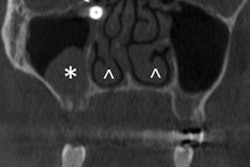

The doctor discovered an off-white color and extra tissue, which turned out to be the bitten nail, on the lingual aspect of the boy's gingival sulcus during a physical exam. The clinician used forceps to remove it. The patient, who didn't receive anesthetic, tolerated the procedure well, according to the authors.

In cases of gingival injury or infection secondary to fingernail biting, clinicians should take a comprehensive dental history and determine any patient history of inserting or ingesting foreign objects. If a foreign object can't be seen, dental imaging can help locate it. However, imaging will not detect a fingernail, so a thorough visual inspection -- including an evaluation of the full dentition, gums, oral cavity, nails, and nail beds -- is key to diagnosis and treatment. Follow-ups also are important, according to the authors.